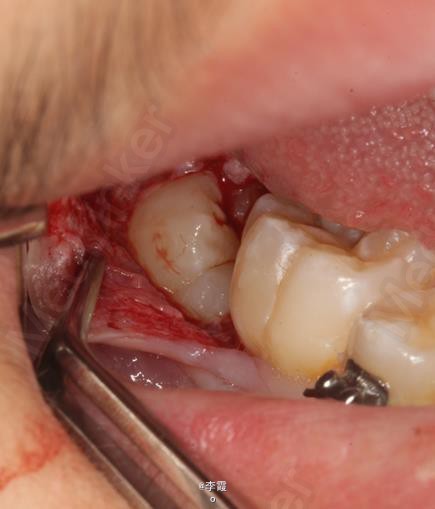

患者、马xx、15岁,主诉:牙齿不齐,要求正畸治疗。 转诊外科行下颌升支处种植体支抗直立下颌磨牙。通过患者的术前影像资料,47牙冠远中有部分骨质覆盖牙冠,采取翻瓣导萌直立磨牙。37采取电刀环切导萌直立磨牙。